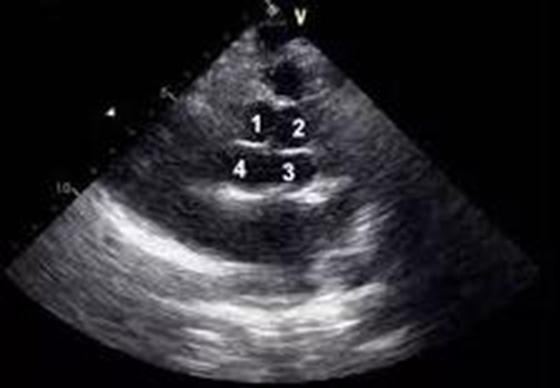

卵圆孔是心脏房间隔胚胎时期的生理性通道,大多数人出生后卵圆孔自然闭合,左、右心房分隔开来。据统计,约四分之一的成人存在卵圆孔未闭合。近年来,越来越多的研究发现:卵圆孔未...